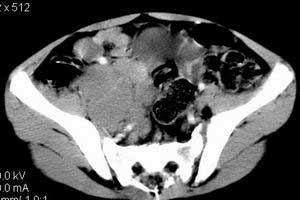

| 患者,男,9岁,因右下腹包块入院,血象不高,不规则发热,常超40度。 平扫: ![]() ![]() ![]() ![]() ![]() ![]() ![]() ![]() ![]() ![]() ![]() ![]() ![]() ![]() ![]() ![]() ![]() ![]() 增强: ![]() ![]() ![]() ![]() ![]() ![]() ![]() ![]() ![]() ![]() ![]() ![]() ![]() ![]() jiajie发言:骶椎右前区不规则软组织肿块,边缘光整,密度均匀,增强后均匀强化,右腹股沟区可见肿大淋巴结,临床有时发热,考虑淋巴瘤,儿童盆腔肿瘤应与神经母细胞瘤和横纹肌肉瘤鉴别。 longzhanghui发言:印象:盆腔右后壁不规则软组织肿块,并向前延伸.似为多个肿块融合,呈中等强化.初步考虑淋巴瘤. 听蝉观竹发言:右侧髂内、外组淋巴结肿大,从其形态和融合的情况看,同意大家意见-----考虑恶性病变,但是9岁男孩还要注意检查睾丸情况,有无隐睾? 常常类似情况是隐睾发生精原细胞瘤淋巴结转移,这个病例也要注意这一点!!! 广东凌发言:大家好,在这里我想说一下个人观点,我建议上传图片的同志能否辛苦一点就是把病史和图片都上传完整一点,比如这个病人的腹膜窗,并且这个病人的肠道的准备也是不怎么好,就从现有的质料看:病灶属于淋巴结肿大当无大的争议,有融合趋势,其内无坏死,边缘强化为主,故考虑:淋巴瘤!建议用腹膜窗看一下和肠道的关系! 阿圣发言:病灶属于淋巴结肿大当无大的争议,有融合趋势,其内无坏死,边缘强化为主,故考虑:淋巴瘤 结果是:淋巴瘤 病例来源:ct762。由宁静致远发布: http://www.radinet.com.cn/forum_view.asp?forum_id=4&view_id=2182 |